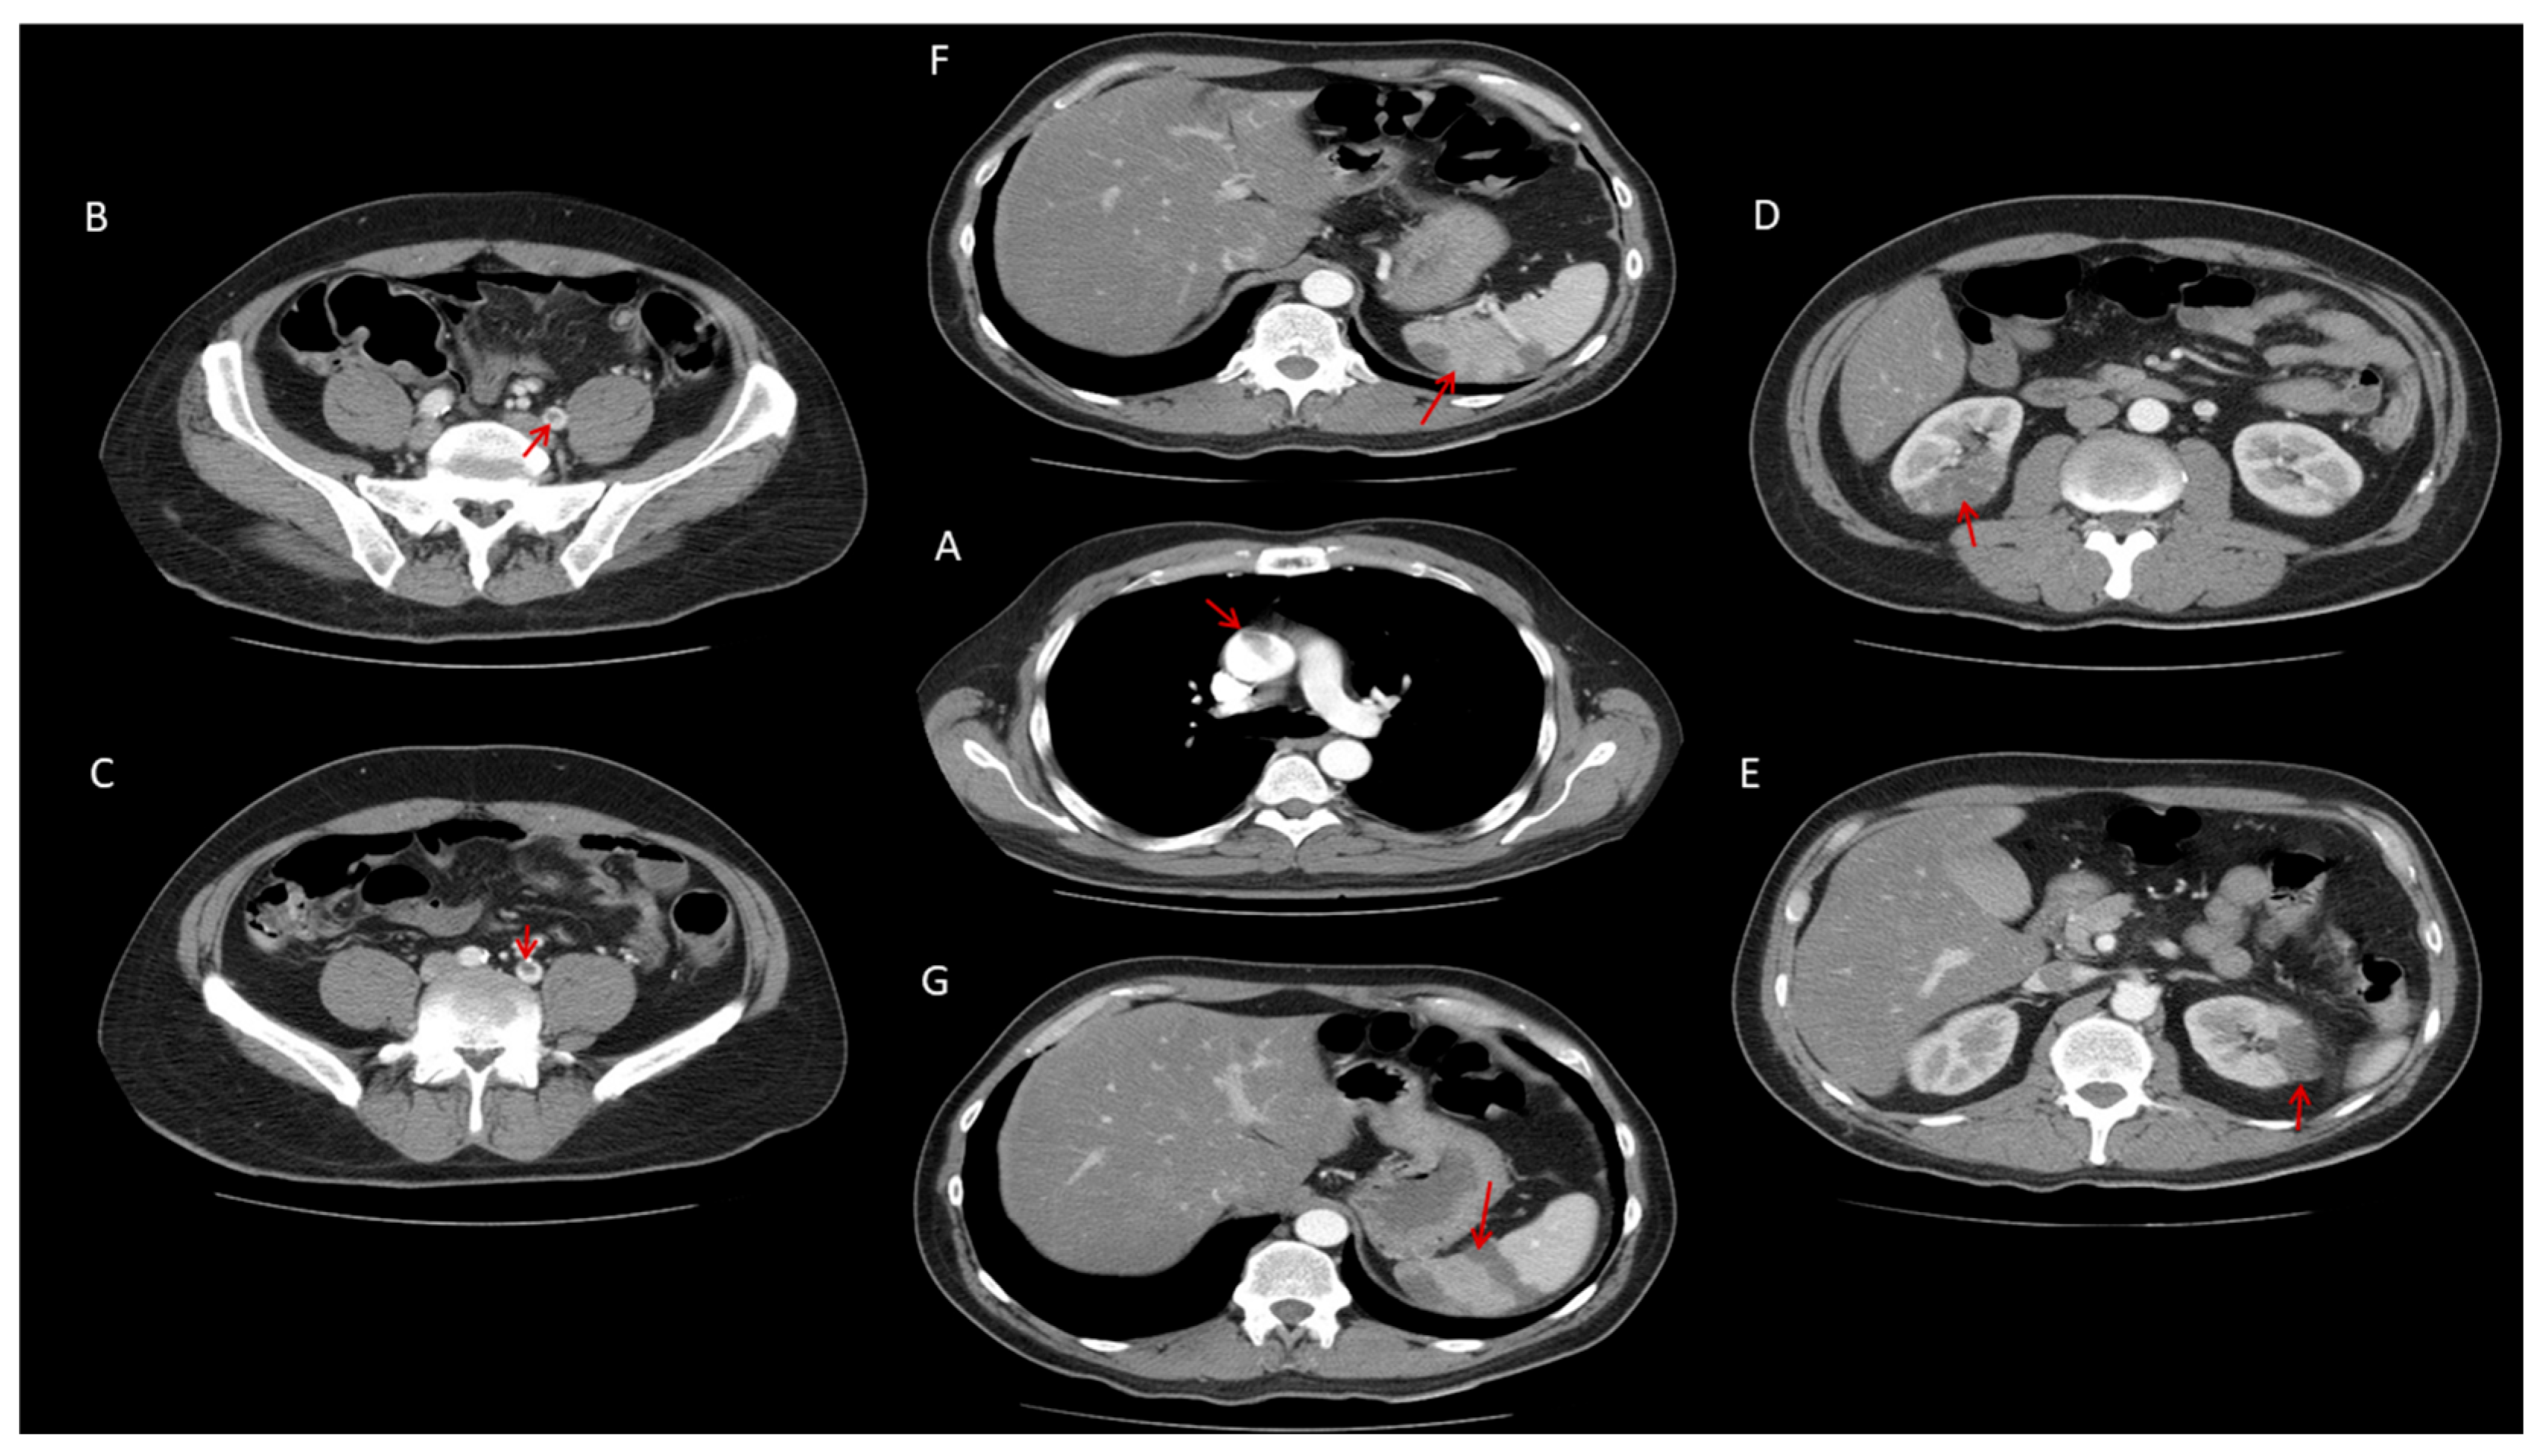

2.4. Neurological and Thrombotic Complications